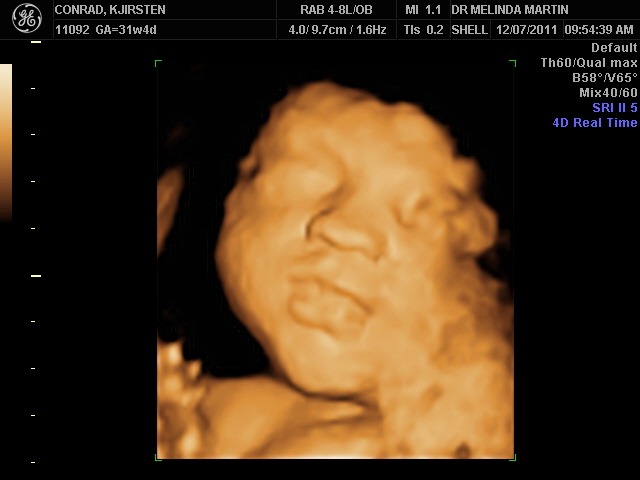

38 Week 3d Ultrasound Baby Picture Pregnancy Symptoms Week By Week

4d Ultrasound 39 Weeks Pregnant Face 4d Rafael Ortega Munoz Ciudad